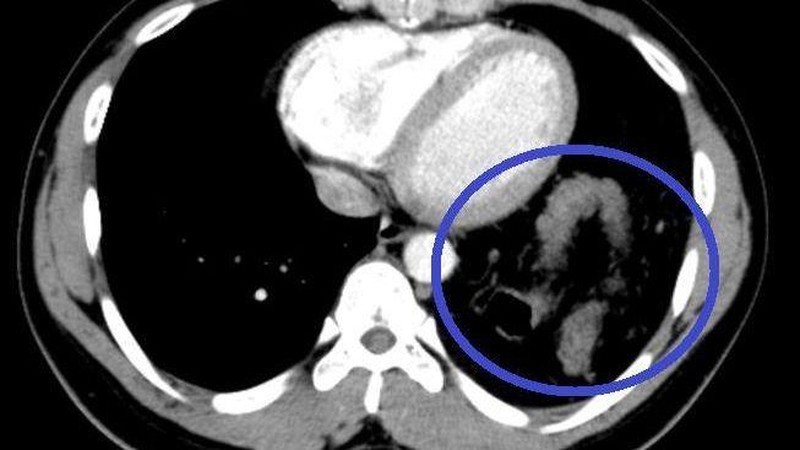

Tại đây, bệnh nhân H. đã được chỉ định mổ nội soi để sửa tổn thương và phục hồi cơ hoành. Khi đưa máy soi vào ổ bụng, phẫu thuật viên nhận thấy gần toàn bộ đại tràng ngang, lách, dạ dày và mạc nối lớn đã chui qua cơ hoành lên khoang màng phổi bên trái.

Sau khi đưa các tạng trên trở lại ổ bụng, tổn thương cơ hoành bên trái lộ rõ là một lỗ khuyết rộng khoảng 6x8 cm. Đây chính là nguyên nhân gây ra thoát vị, kết hợp với tiền sử có chấn thương, chẩn đoán trong mổ là thoát vị hoành trái do vỡ cơ hoành.

Một số phương pháp chẩn đoán hình ảnh được chỉ định để chẩn đoán thoát vị hoành: Chụp X.quang: Dấu hiệu mất liên tục vòm hoành, có hình ảnh mức nước hơi của quai ruột trong lồng ngực; Chụp cắt lớp vi tính và cộng hưởng từ: Thấy vị trí gián đoạn của cơ hoành, hình ảnh các tạng thoát vị, giúp đánh giá được thể bệnh và đưa ra phương án điều trị phù hợp.